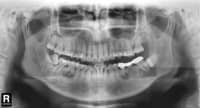

為什么一定要拍片?它有可能會救你命!!

患者是30多歲的年輕男子,紅色標(biāo)記那顆牙松動,要求拔牙,開始嫌麻煩不愿拍片,后來經(jīng)過再三勸說還是拍了片。結(jié)果把所有人包括他自己都嚇了一跳......